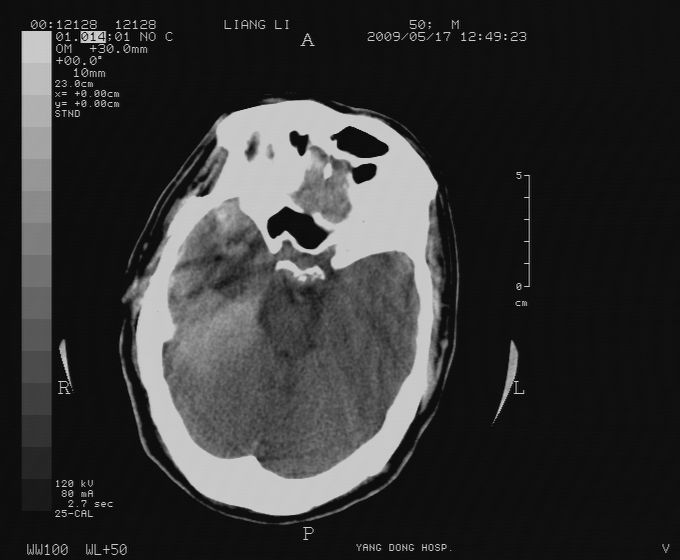

以下是引用zjzjr在2009-5-18 11:26:00的发言:[br]右颞枕叶及基底节区脑出血破入脑室系统,蛛网膜下腔出血,右枕顶部硬膜下血肿.颅骨及颅内低密度软化灶为血肿清除术后改变.

以下是引用随光逐影在2009-5-18 14:47:00的发言:[br]支持 右颞枕叶及基底节区脑出血破入脑室系统;蛛网膜下腔出血;右枕顶部及右侧天幕硬膜下血肿。右侧颅骨术后改变;颅内低密度软化灶为血肿清除术后改变。